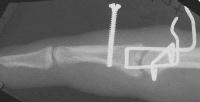

Clinical Example: PIP fracture dislocation treated with force couple splint

Proximal interphalangeal joint fracture dislocation is a common and difficult injury. There are many possible treatment techniques. Here, the force couple splint method was used.